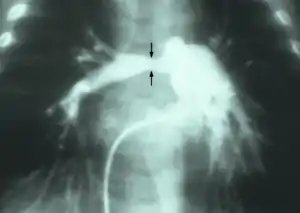

| Stenosis of the right pulmonary artery in a patient which was due to a case of congenital rubella. | |